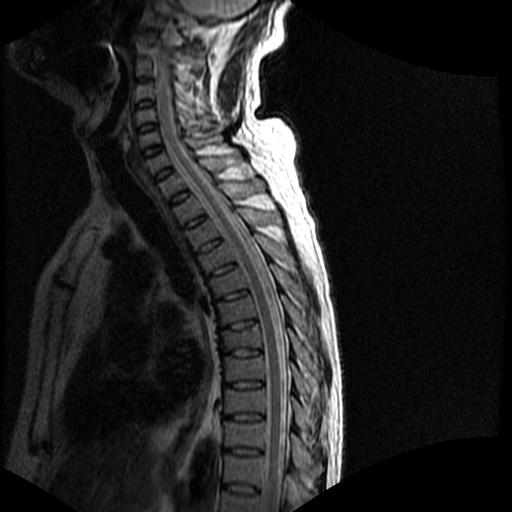

68岁男性,胸部疼痛,不适。

t7椎体前1/3信号略减低,椎体上下面凹陷,相应脊髓几周边软组织信号未见改变。考虑:椎体退变。

陈旧性压缩性骨折

胸7椎体楔状变形及信号异常,附件未见明显异常信号.椎间隙正常.未见软组织块影.考虑骨质疏松所致压缩性骨折可能大.

胸7椎体楔状变形及信号异常[t1t2 均为低信号],附件未见明显异常信号.椎间隙正常.未见软组织块影.考虑陈旧性压缩性骨折伴退变。

首先需除外单发成骨性转移瘤可能。

转移瘤也不能排除